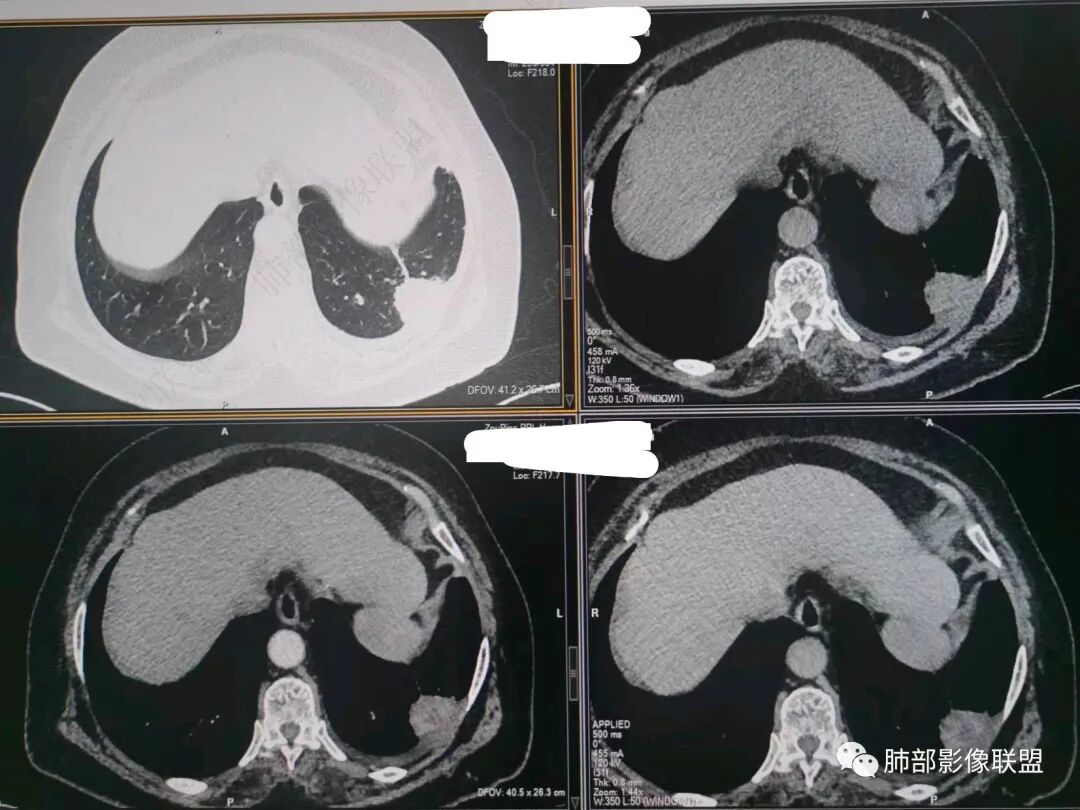

南边:今天的病例肺内部分基本都是炎性特点,问题就在于胸膜。

糊墙:肺内病灶不侵犯壁层胸膜或以外,与壁层胸膜相对而言分界清楚。

栽赃:病灶侵入壁层胸膜及胸膜外脂肪间隙、胸壁其他结构等,相对在病灶中央区域,与胸膜分界不清。

南边:看肺内病灶与胸膜分界清,增强后强化不一致,需要综合分析。

这是糊墙。

这就栽赃。都突到外面去了。

看看这个,骨头都侵袭了。

今天的病例有些伪影。

看起来就觉得放射状伪影。

我就不知道这些是胸水,伪影导致密度增高?还是胸膜增厚?

我只是邓较瘦:今天平扫的像栽赃, 增强感觉是增厚的胸膜。

南边:一般这类侵袭,是中央地带毛刷状延伸到胸膜内。

而且旁边这么宽的少,所以觉得很奇怪,不太符合,我是怀疑与照片有关。

你对比一下两侧的密度。肌肉密度不一样。